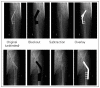

Example of creative techniques to blind radiographs of femoral neck fracture reduction, fixated with either a dynamic hip screw or 3 cannulated screws.